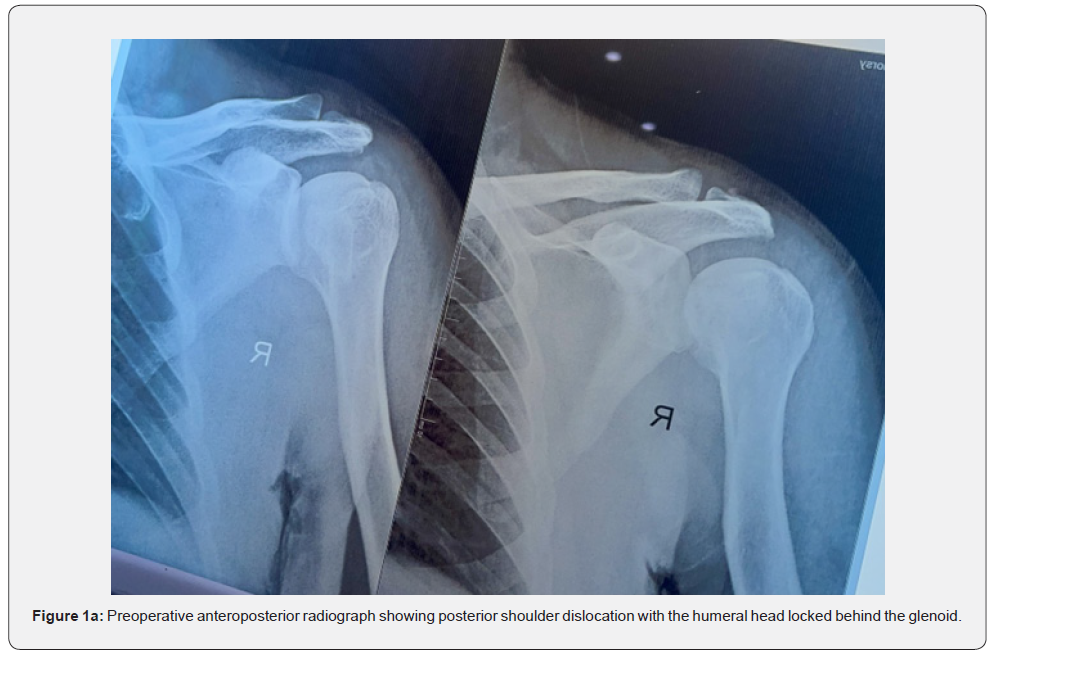

Preoperative anteroposterior and axillary radiographs demonstrated a neglected locked posterior shoulder dislocation with a reverse Hill–Sachs defect (Figure 1a). Computed tomography and MRI confirmed a posteriorly locked humeral head with approximately 30% involvement of the articular surface (Figure 2a–2d).

Intraoperative fluoroscopic images further delineated the light bulb sign and locked position of the humeral head (Figure 3).